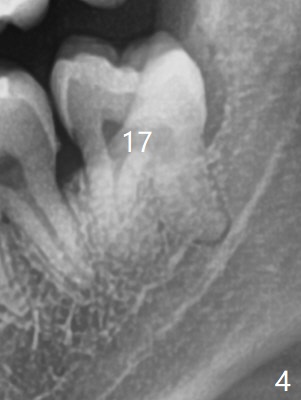

A 26-year-old man presents to clinic with pericoronitis at #17; the tooth #16 bites on the distal swollen gingiva of the tooth #17 (Fig.1). Since there appears to be no bone loss distal of #18, collagen plug, instead of Osteogen plug (Fig.2,3), will be placed in the socket(s) after extraction (Fig.4,5). For easy insertion, the plug is cut apically (Fig.6 *). The wound is closed with 4-0 plain gut suture. The patient returns for #1 and 32 extraction, eight months post #16 and 17 extraction. As usual, no bone substitute is placed in #1 socket after extraction (Fig.7). After #32 extraction, the distal socket looks large so that Augma (Bond Apatite) is placed and pressed (A), followed by a piece of Collagen Plug (C, to prevent Augma dissolved by saliva in case premature loss of suture). In fact there is also buccal defect at #32 due to chronic infection and heavy calculus. There is cortical bone formation at #16 socket opening (^). The mesial and distal sockets of #17 (*) seem to be obliterated because of placement of Collagen Plug. Return to Plug, Weichat Xin Wei, DDS, PhD, MS 1st edition 01/05/2019, last revision 09/22/2019